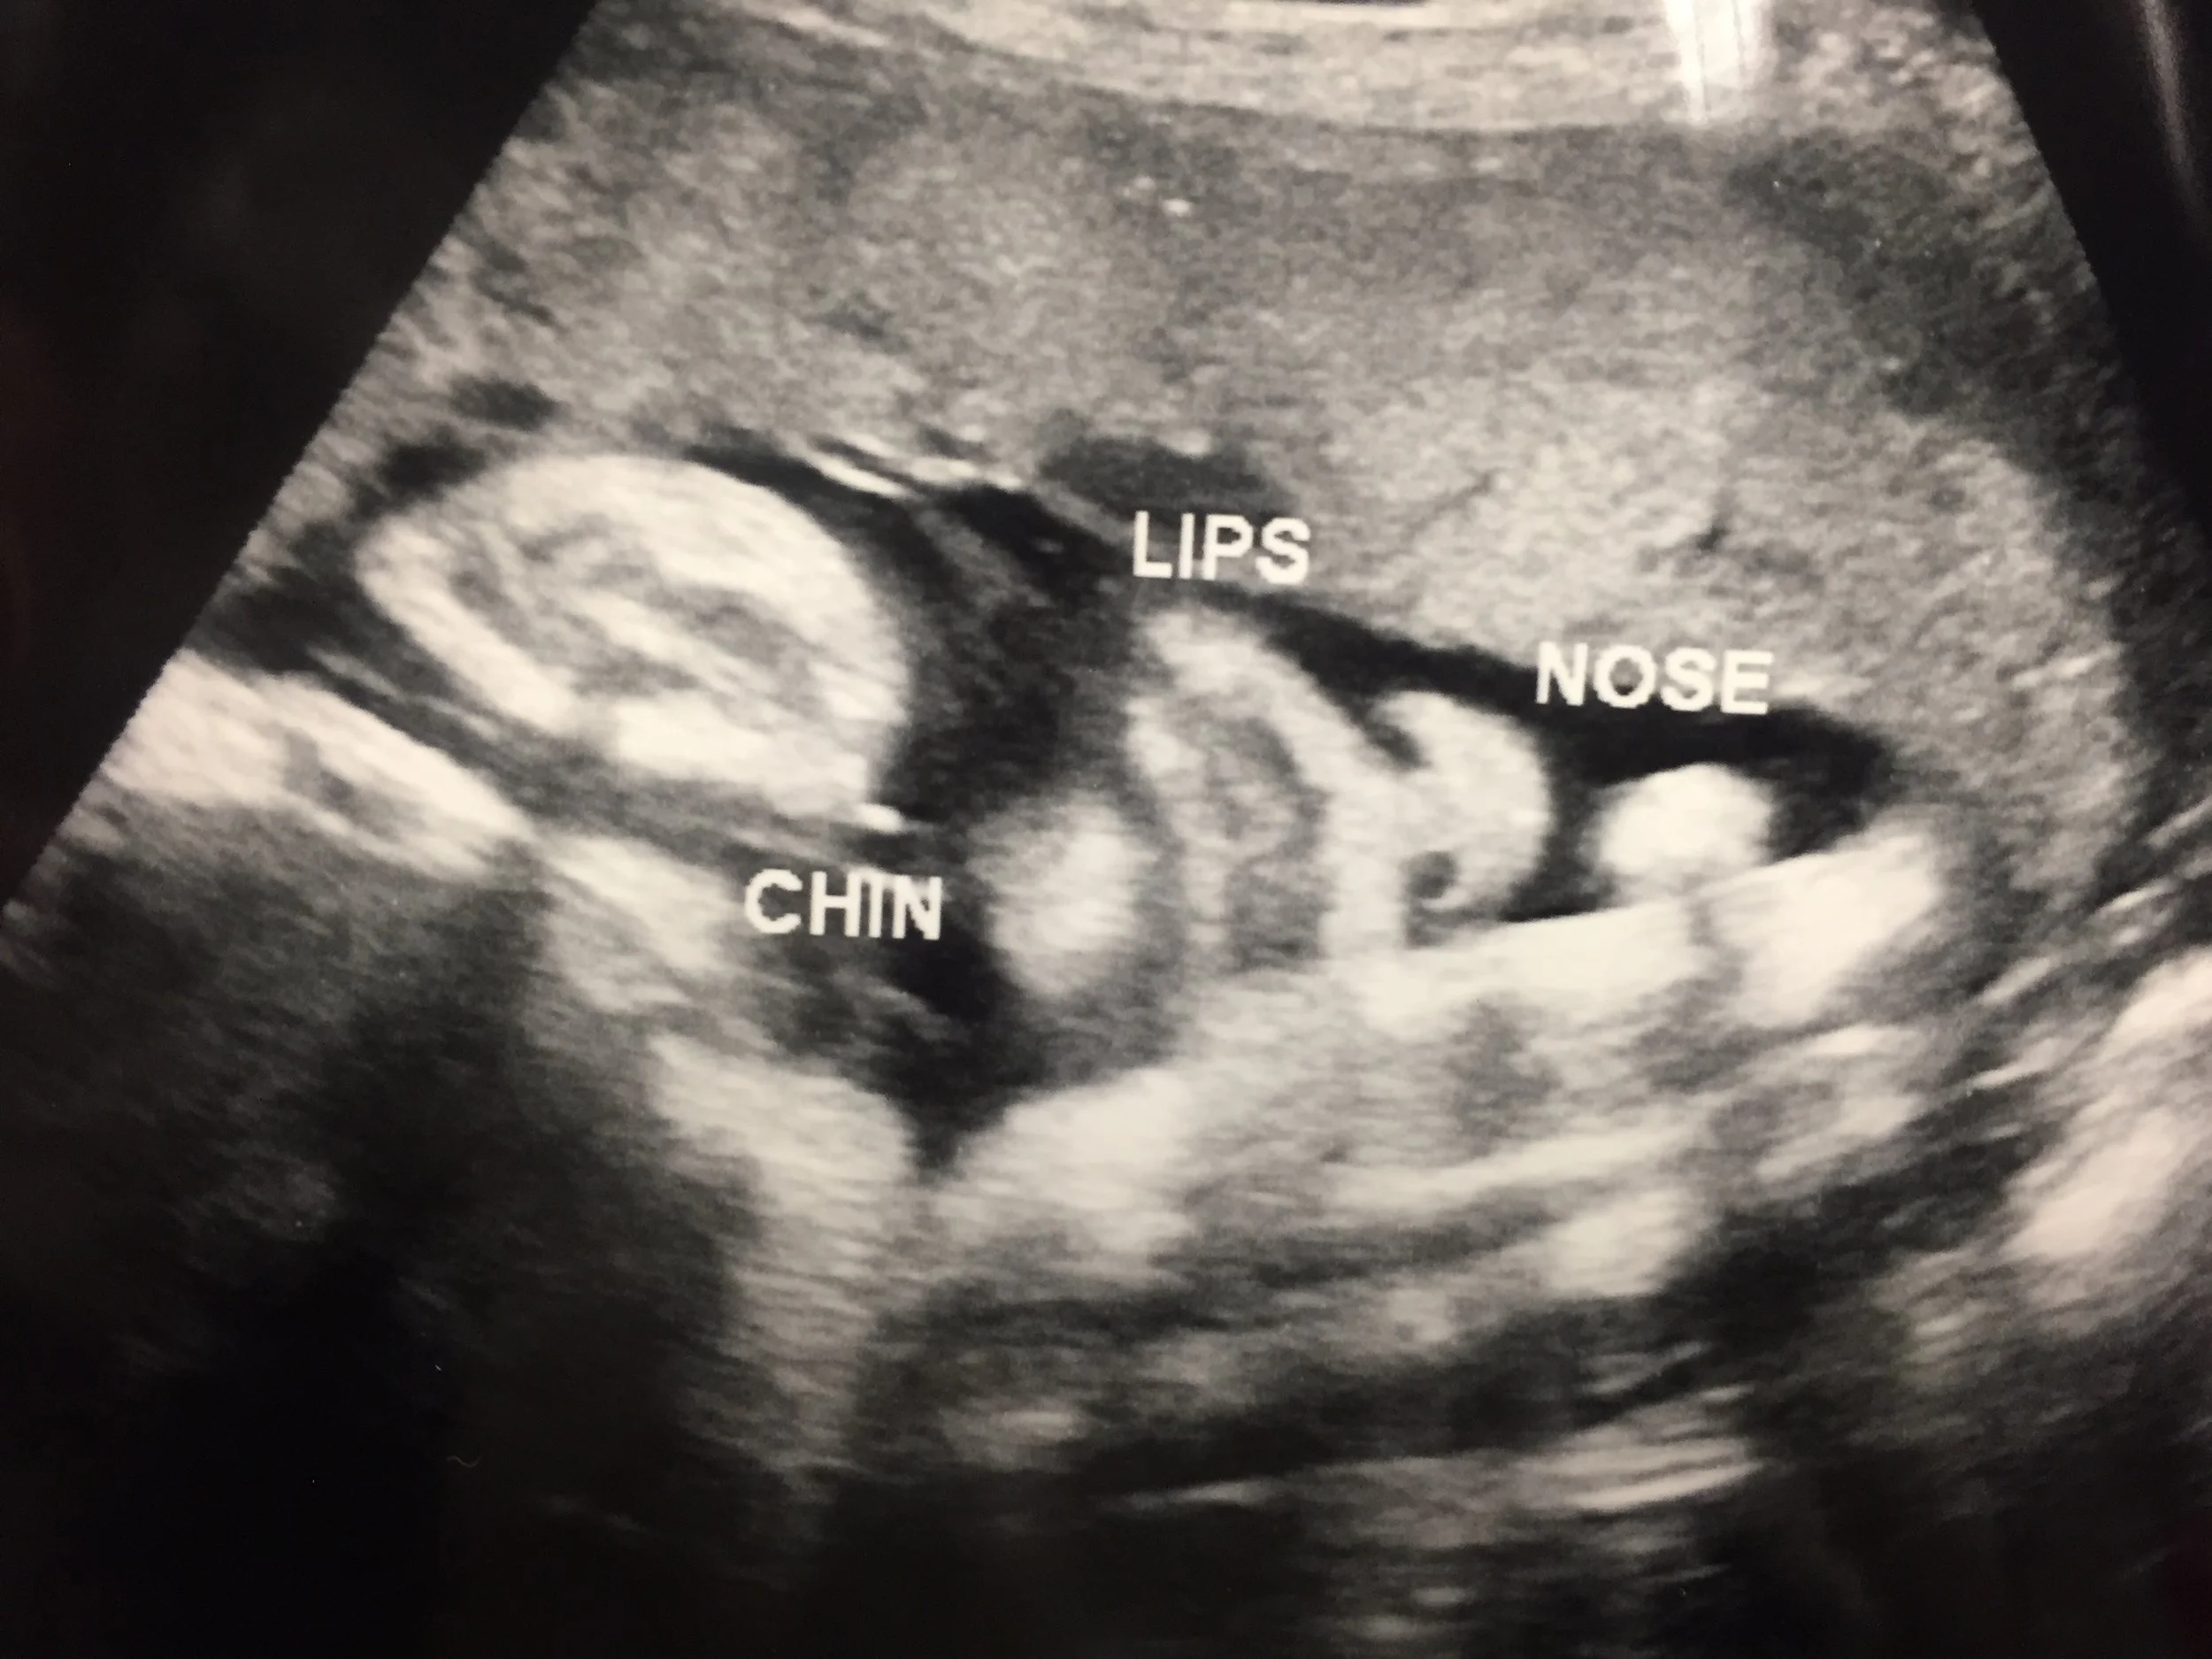

I love this photo of the front of the baby's face. The ultrasound was showing chubby cheeks and hair. :)